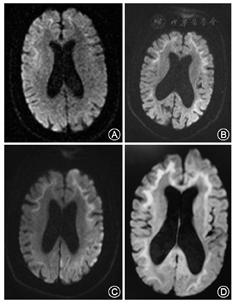

患者女性,61岁,家庭主妇。主因"反复发作性意识模糊7年,再次发作4 d"于2017年3月20日收入我院。患者于2010年2月1日无明显诱因出现意识模糊、胡言乱语,不能与人沟通,不伴发热、肢体无力、肢体抽搐等,症状持续约1 h后消失,当时检测血糖水平在正常范围。2 d后出现剑突下胀痛,反复非喷射性呕吐,呕吐物为胃内容物,出现流涎,我院消化内科给予胃黏膜保护剂、止吐药、胃肠动力药物等对症治疗,仍然间歇性上腹疼痛和呕吐,症状持续2个月逐渐好转。2010年6月开始患者出现反复发作性意识模糊,不能识别家人和朋友,无法言语沟通,每年发作2~3次,症状类似于2010年首次发作,每次持续半小时至数小时不等,经补液或自行好转。2016年2月及8月分别出现间歇性上腹痛、呕吐及流涎,症状波动迁延达2个月余,逐渐自行缓解。2017年3月16日患者再次出现意识模糊,并出现言语不能,右侧上、下肢活动较左侧显著减少,尿潴留。无发热、肢体抽搐和活动障碍等。家人发现自2010年患者记忆力逐渐减退,以近记忆力下降显著,如反复询问刚刚发生的事情,不能完整做完一项任务等,发作性症状间期能够从事简单的家务活动。患者于2012年行"胆囊切除术"史。无高血压、糖尿病、心脏病、肝炎及结核史,家族中无类似病史。入院检查:心、肺未见异常,腹壁软,肝脾未触及肿大,肠鸣音正常。嗜睡,意识内容减少,混合性失语,神经系统检查不能配合,双侧瞳孔等大等圆,对光反应存在,眼球运动充分,右侧肢体主动活动较左侧减少,疼痛刺激可见右上下肢肌力小于左侧。共济运动、深浅感觉检查不能配合。四肢腱反射减低,双侧掌颏反射和吸吮反射阳性,双侧巴宾斯基征阴性。颈软,脑膜刺激征阴性。辅助检查:甲状腺功能及甲状腺过氧化物酶抗体、肿瘤标志物、免疫全套、抗中性粒细胞胞质抗体、血氨、血乳酸、肌酸激酶及同工酶等均在正常范围。脑脊液常规及生化检查结果正常,脑脊液和血自身免疫性脑炎及副肿瘤相关抗体均为阴性。尿有机酸及血脂酰肉碱及氨基酸检测未见异常。腹部X片及腹部CT未发现肠梗阻,胰腺MRI平扫及增强未发现胰腺占位,胃镜显示慢性非萎缩性胃炎。神经传导检测与针极肌电图检查结果示:上下肢运动和感觉神经传导速度检测均在正常范围,F波出现率、潜伏期均正常;皮肤交感反应(SSR)检测:双侧上、下肢SSR均未引出波形。左肱二头肌活检病理检查:肌纤维大小形态正常,肌质和核内未见异常物质沉积,改良Gomori三色染色未见不整红边纤维。线粒体DNA热点突变位点(mtDNA-3243、3271、3260、8344、8356和8993)筛查均为阴性。头颅MRI动态变化:2010年2月4日弥散加权成像(DWI)可见双侧额叶沿皮髓质交界处高信号影;2017年3月19日DWI可见双侧额、顶、颞、枕叶沿皮髓质交界处对称性绸带状高信号影,左侧额、顶、颞、枕叶皮质多发斑片状高信号影;2017年3月23日DWI可见双侧额、顶、颞、枕叶沿皮髓交界处分布对称性绸带状高信号影,左侧额、顶、颞、枕叶皮质多发斑片状高信号影,皮质区病灶较2017年3月19日范围略扩大;2017年4月20日DWI可见双侧额、顶、颞、枕叶沿皮髓交界处分布对称性绸带状高信号影,与前2次比较,左侧额、顶、颞、枕叶皮质病变大部分消失(图1)。皮肤病理改变:HE染色可见部分汗腺腺体细胞、脂肪细胞和纤维母细胞细胞核内存在嗜酸性核内包涵体,免疫组织化学染色可见包涵体泛素和p62阳性。电镜可见汗腺腺体细胞、脂肪细胞和纤维母细胞的细胞核内类圆形包涵体,大小约1.5 μm×5 μm,由纤维样物质构成,周边有晕(图2)。治疗及病情演变:入院后给予对症支持治疗,第4天患者意识转清,检查发现存在混合性失语。入院后第2天右侧肢体肌无力进行加重,并于第7天进展至右侧肢体肌力0级,第11天开始右侧肢体肌力逐渐恢复,并开始能听懂他人言语。第19天出现上腹部疼痛,反复呕吐,流涎,消化道症状与2010年及2016年2次发作完全一致,持续20 d左右症状消失。入院后第45天,右肢肌力恢复至Ⅳ级,运动性失语。

NIID患者头颅MRI T2WI和FLAIR序列可出现明显的脑白质病变,这些白质病变在T2WI双侧对称并相互融合,T2WI高信号的区域在T1WI呈低信号。DWI可出现特征性沿皮质、髓质交界处高信号,病灶随着疾病进展不断向后延伸[9]。正如本例患者2010年的MRI表现,DWI高信号病灶仅存在于额叶皮髓质交界处。随着病程进展,至2017年,DWI高信号病灶从额叶向顶枕叶延伸。即使病程到了无动性缄默晚期,T2WI出现广泛的脑白质病变时,DWI高信号也不会累及深部白质。DWI沿皮质、髓质交界处高信号改变,是NIID特征性影像表现,在散发型病例中的出现率为100%,而在家族型病例中的出现率为(81.8%)[7]。DWI的这种特征性影像学改变尚未见于其他疾病的报道,该影像学特征对于诊断NIID具有很高的提示价值,我们将这种特征性影像命名为皮质下绸带征(subcortical lace sign)。